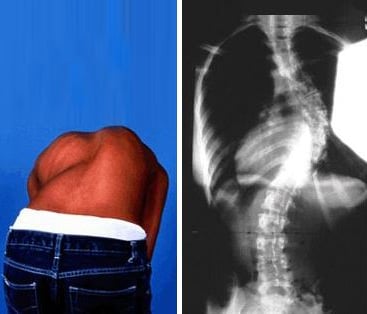

غالبًا ما يتطوّر الجنف بشكل تدريجي وقد لا يسبب ألمًا واضحًا في مراحله المبكرة. كثير من الأفراد — سواء الأطفال أو البالغين — قد لا يدركون إصابتهم بالجنف إلا بعد ملاحظة تغيّرات في وضعية الجسم أو وجود عدم تماثل واضح. ويساعد فهم العلامات الشائعة للجنف في تحديد ما إذا كان من المناسب إجراء تقييم مهني.

يؤثر الجنف على محاذاة العمود الفقري ووضعية الجسم. قد تستفيد أنت أو طفلك من إجراء تقييم إذا لاحظتم واحدًا أو أكثر من العلامات التالية:

بروز في الأضلاع أو الظهر

عند الانحناء إلى الأمام (مثل ربط الحذاء)، قد يبدو أحد جانبي القفص الصدري أو أسفل الظهر أعلى أو أكثر بروزًا من الآخر — وهي علامة شائعة على دوران العمود الفقري المرتبط بالجنف.